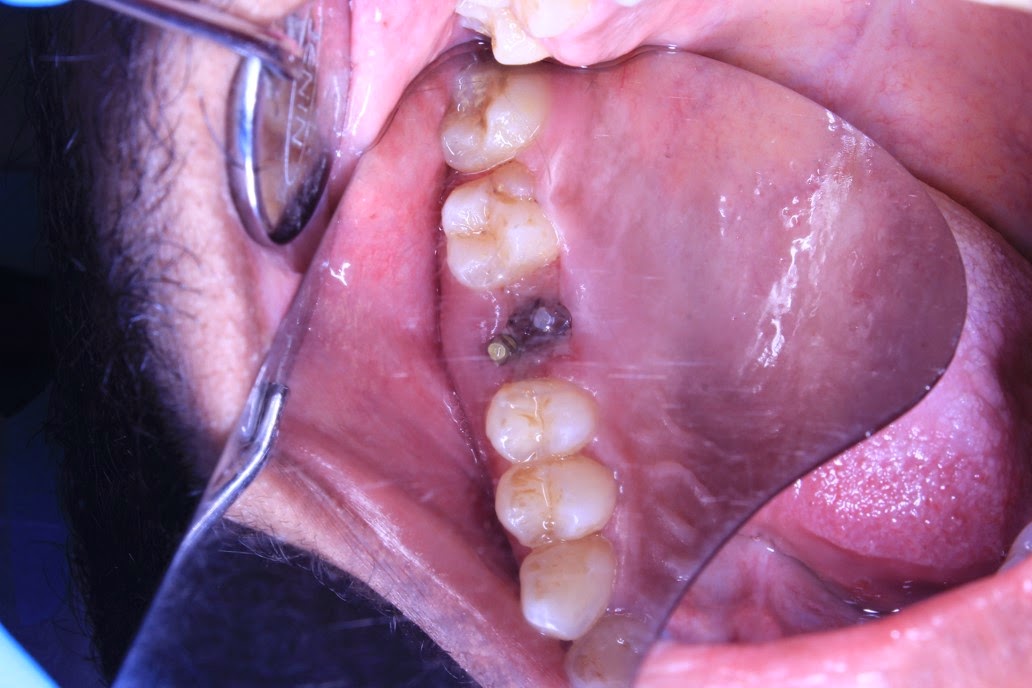

Acute Pericoronitis Does It Hurt To Get A Molar Removed Gum tissue is likewise at risk of infection. Dental professionals have done a good. | how common is feeling pain? Having your teeth removed can be frightening and even worse when it comes to molar tooth extraction. While many people shudder when they think about having a tooth extracted, part of the reason for their worry is what happens after. Does It Hurt To Get A Molar Removed.